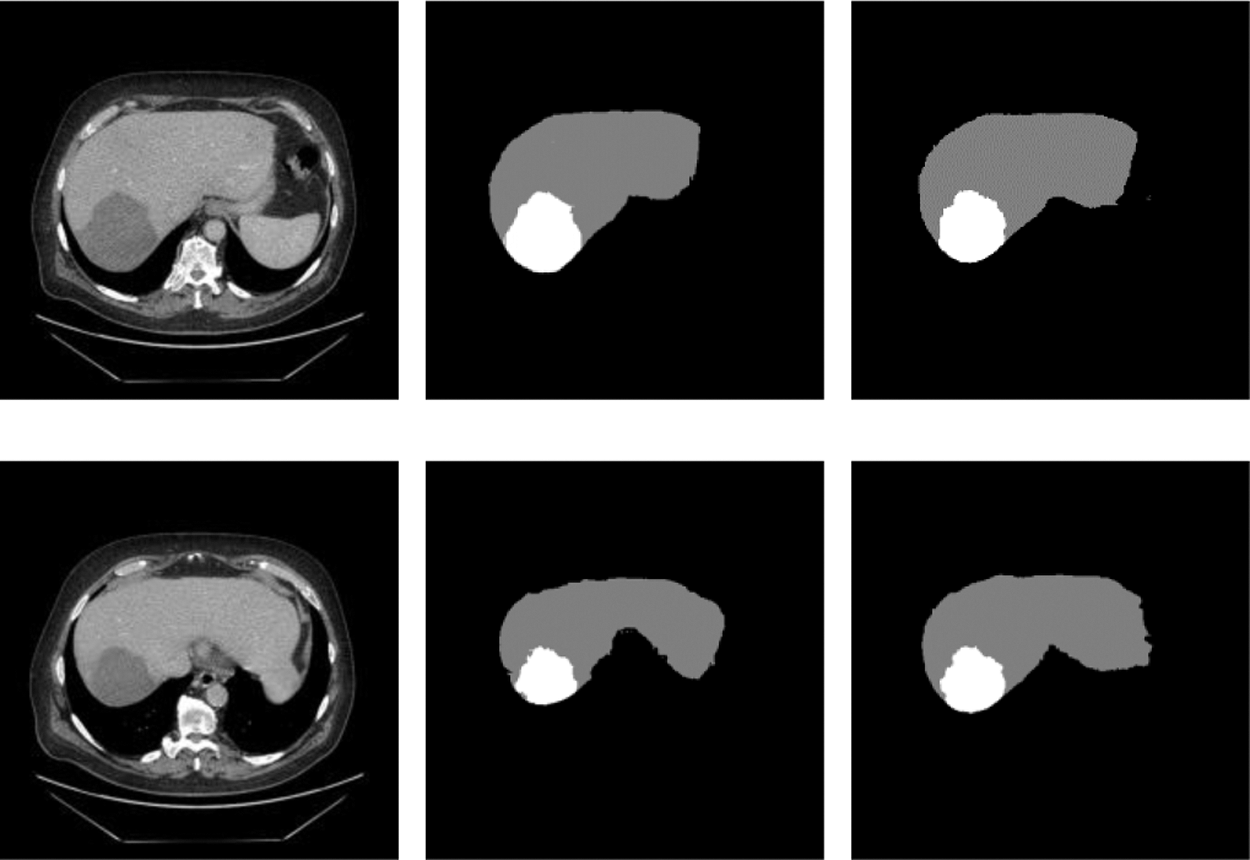

In order to prove that the two new modules designed in this network and the adaptive weighted cross-entropy loss function achieved superior results for liver and tumors segmentation, the ablation experiments were first performed and the trained model was tested on the test set, and the segmentation results are shown in the Fig. 6. It indicated the test results of the proposed network for liver and tumors segmentation together with the results of manual annotation by experts.

From Fig. 7, we can see that the segmentation results obtained from the model designed in this paper were very close to expert annotation images, and this method can effectively optimize the border details of liver and tumor and solve low contrast and complex areas problems.

Figure 7: Raw, ground truth and segmentation results on the test image

We wanted to verify the effectiveness of the model for completing segmentation tasks, so we will compare the test results about Dice. The details of the comparison can be seen in Tab. 1. From the data in the table, we can find that the performance has been slightly improved after adding ECSA and FPRM separately; and after using cross-entropy loss function for adaptive weights, the performance has been better improved. This also verifies the efficiency of this model.

When we conducted comparative experiments, five metrics are used to measure the accuracy of segmentation results, including the volumetric overlap error (VOE), relative volume difference (RVD), average symmetric surface distance (ASSD), root mean square symmetric surface distance (MSD) and DICE. Tabs. 2 and 3 made clear results of comparing the proposed method with other segmentation algorithms. It can be seen that the Dice of the proposed network model in segmenting the liver was 0.965, and the values of other indicators were also relatively high. The Dice of segmented tumor was 0.672, which stated clearly that the network structure was more stable.

Although the Dice of H-DenseUNet was slightly higher, it used 3DdenseUNet that required higher conditions for hardware acceleration operations. The model we proposed can complete the segmentation of liver and tumors under the condition of low hardware requirements. It also fully proved that the modules designed by us effectively optimized the segmentation results both and obtained more accurate predicted target areas of CT scan abdominal images.